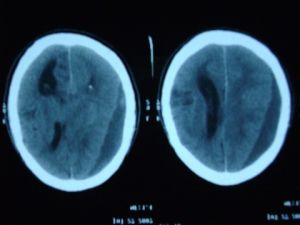

引起腦疝原因:顱內任何體積較大的占位病變引起顱腔內壓力分布不均時都可引起腦疝。病變在幕上者引起小腦幕切跡疝,病變在幕下者引起枕骨大孔疝。引起腦疝的常見病變有:①損傷引起的各種顱內血腫,如急性硬腦膜外血腫、硬腦膜下血腫、腦內血腫等;②各種顱內腫瘤特別是位於一側大腦半球的腫瘤和顱後窩腫瘤;③顱內膿腫;④顱內寄生蟲病及其他各種慢性肉芽腫。在上述病變的基礎上如再附加一些人為的因素,例如作腰椎穿刺釋放過多的腦脊液,使顱腔與椎管之間、幕上分腔與幕下分腔之間的壓力差增大,可促使腦疝的形成。這種由於醫源性因素造成的腦疝,臨床醫師應予避免。

臨床症狀

腦疝症狀1.顱內壓增高的症狀:表現為劇烈頭痛及頻繁嘔吐,其程度較在腦疝前更形加劇,並有煩躁不安。

2.意識改變:表現為嗜睡、淺昏迷以至昏迷,對外界的刺激反應遲鈍或消失。

3.瞳孔改變:兩側瞳孔不等大,初起時病側瞳孔略縮小,光反應稍遲鈍,以後病側瞳孔逐漸散大,略不規則,直接及間接光反應消失,但對側瞳孔仍可正常,這是由於患側動眼神經受到壓迫牽拉之故。此外,患側還可有險下垂、眼球外斜等。如腦疝繼續發展,則可出現雙側瞳孔散大,光反應消失,這是腦幹內動眼神經核受壓致功能失常所弓[起。

4.運動障礙:大多發生於瞳孔散大側的對側,表現為肢體的自主活動減少或消失。腦疝的繼續發展使症狀波及雙側,引起四肢肌力減退或間歇性地出現頭頸後仰,四肢挺直,軀背過伸,呈角弓反張狀,稱為去大腦強直,是腦幹嚴重受損的特徵性表現。

5.生命體徵的紊亂:表現為血壓、脈搏、呼吸、體溫的改變。嚴重時血壓忽高忽低,呼吸忽快忽慢,有時面色潮紅、大汗淋漓,有時轉為蒼白、汗閉,體溫可高達41℃以上,也可低至35℃以下而不升,最後呼吸停止,終於血壓下降、心臟停搏而死亡。